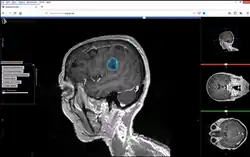

Brain Tumor Segmentation under Studierfenster.

Studierfenster or StudierFenster (SF)[1][2][3] is a free, non-commercial open science client/server-based medical imaging processing online framework. It offers capabilities, like viewing medical data (computed tomography (CT), magnetic resonance imaging (MRI), etc.) in two- and three-dimensional space directly in the standard web browsers, like Google Chrome, Mozilla Firefox, Safari, and Microsoft Edge. Other functionalities are the calculation of medical metrics (dice score[4] and Hausdorff distance[5]), manual slice-by-slice outlining of structures in medical images (segmentation[6][7]), manual placing of (anatomical) landmarks in medical image data, viewing medical data in virtual reality, a facial reconstruction and registration of medical data for augmented reality,[8] one click showcases for COVID-19 and veterinary scans, and a Radiomics module.

Other features of Studierfenster are the automatic cranial implant design with a neural network,[9][10] the inpainting of aortic dissections[11] with a generative adversarial network,[12][13] an automatic aortic landmark detection with deep learning[14] in computed tomography angiography scans, and a GrowCut algorithm implementation for image segmentation.